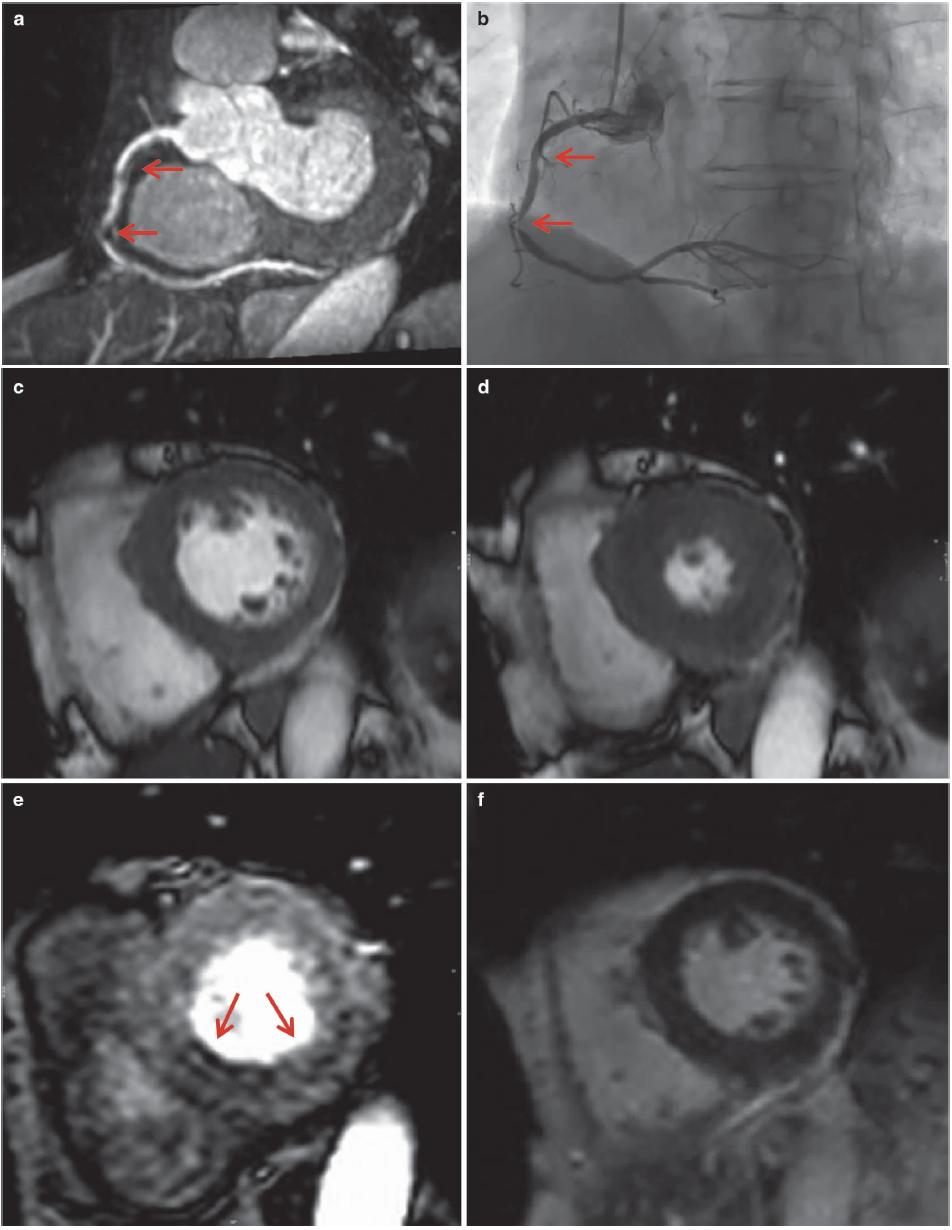

图7.8 心肌缺血,RCA明显狭窄。患者女性,69岁,胸痛。注射0.15mmol/kg钆喷酸葡胺后,通过使用平衡相中的脂肪饱和脉冲获得梯度回波三维CMRA图像(TR/TE,4.2/2.1ms;翻转角度,20°;SENSE因子4;FOV 280mm×280mm×120mm;采集矩阵256×256×80;重建矩阵512×512×160)。

(a)全心冠状动脉MR造影MIP图像显示RCA明显狭窄(箭头)。(b)冠状动脉MR造影与冠状动脉造影(箭头)之间存在良好的一致性。(c)舒张末期的短轴电影MR图像和(d)收缩末期未见明显的区域性室壁运动异常。(e)负荷心肌灌注MR图像显示下壁(箭头)缺血,其对应于RCA供血区域。(f)晚期钆增强MR图像未见心肌瘢痕。